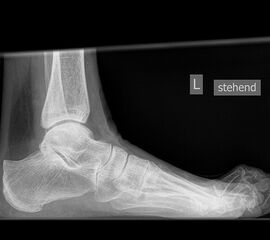

Sprunggelenk lateral mit Belastung

Positionierung:

• Der Patient steht, beide Beine sind geleichmäßig belastet.

• Der Zentralstrahl wird ist in Höhe des Gelenkspalts des OSG auf die dorsale Kante der Fibula zentriert.

• Die Kassette liegt medial dem Fuß an und ist parallel zur Fußachse ausgerichtet.

Kennzeichen des Röntgenbildes:

• Tibiagelenkfläche und Talusrolle werden exakt seitlich dargestellt, es kommt zu keinen Doppelkonturen.

• Die Fibula projiziert sich ins mittlere bis hintere Drittel der Tibiagelenkfläche.

• Die vordere und hintere Tibiakante, das Chopart-Gelenk und das Subtalargelenk kommen zur Darstellung. Das proximale Ende des Os metatarsale V ist mit abgebildet. Der Weichteilmantel (Achillessehne) ist erkennbar.

• In der belasteten Situation kommen insbesondere Verschiebungen von Talus gegenüber der Tibia zur Darstellung sowie eine Verschmälerung des Gelenkspalts.

Besondere Bemerkungen zum Beispielbild:

• Zustand nach Fremdkörperverletzung (2. Ebene zur Mortise-Aufnahme unter Belastung).

• Die röntgendichte Struktur (Metall) befindet sich plantar im Bereich des Kalkaneus.